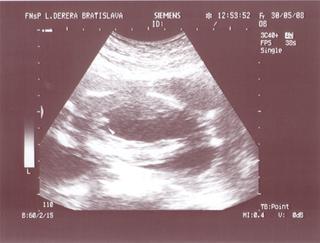

@bv_alexandra 3Dčko je skôr pre potešenie, morfologický UV je na diagnostiku, vidno na ňom orgány a kosti bábätka, vidno chlopne srdiečka, je možné zmerať dĺžku kostí a tak podobne, len pre porovnanie, už som to sem dávala aj predtým a písala som o tom, pridávam ti fotky z môjho prvého tehu, tie "farebné" sú z 3Dčka tam je krásne vidieť bábätko, tváričku, črty tváre, je vidieť na koho sa podobá, ako vyzerá, na morfologickom, to je ten čiernobiely vidieť bábo "zvnútra" aby sa potvrdilo že je úplne zdravé a nemá žiadne vývojové vady, podľa dĺžky kostí ti tam aj spresnia termín pôrodu.